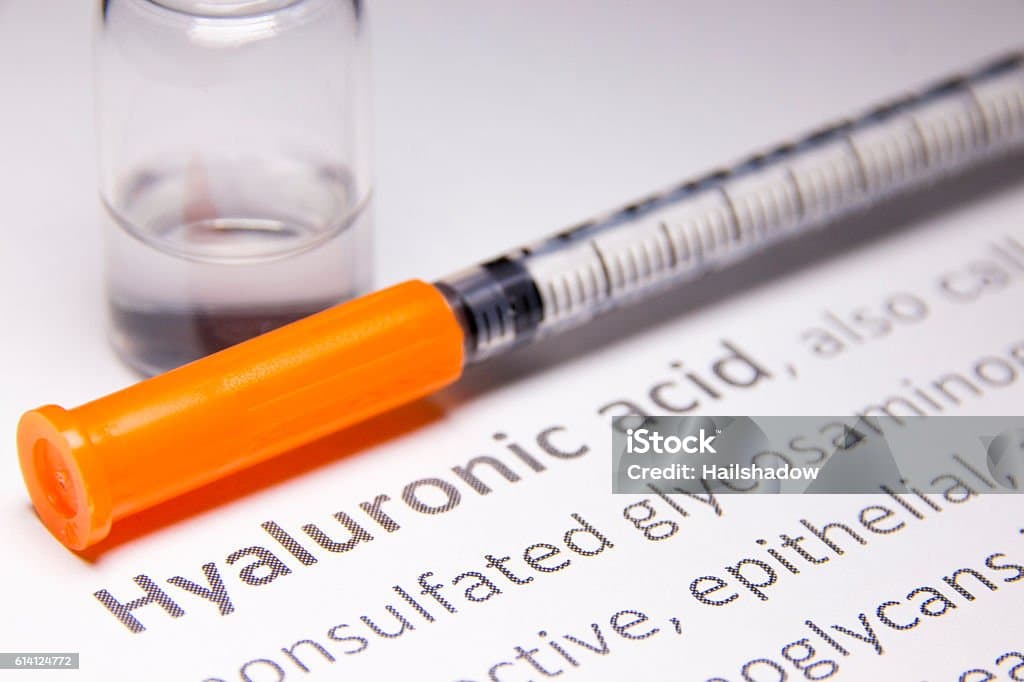

- Wirkungsweise: Durch die Injektion von "künstlicher Gelenkschmiere" wird die Reibung im Gelenkspalt reduziert. Dies entlastet den Knorpel und kann Schmerzen lindern.

- Ablauf: Die Behandlung erfolgt meist in einem Zyklus von 3 bis 5 Injektionen im wöchentlichen Abstand.